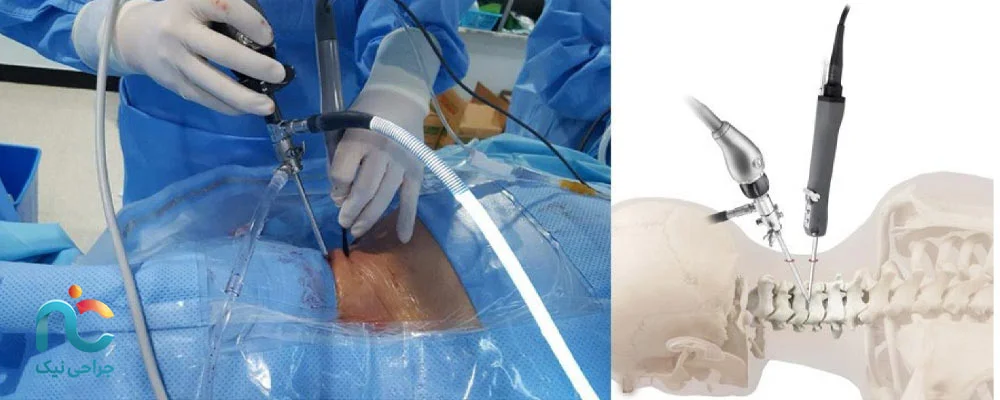

اگر بخواهیم ساده بگوییم، جراحی اندوسکوپیک دیسک گردن یعنی درمان دیسک با کمترین برش ممکن و بدون آسیب به ساختارهای اطراف ستون فقرات. در این روش، به جای باز کردن گردن با برشهای بزرگ، از یک لوله باریک و دوربین مخصوص استفاده میشود که داخل آن منبع نور و ابزارهای جراحی قرار دارند. این دوربین تصویر دقیقی از محل بیرونزدگی دیسک را روی مانیتور نشان میدهد و جراح دیسک گردن میتواند با دقت میلیمتری، قسمت آسیبدیده را خارج کند یا فشار را از روی عصب بردارد.

در کل، اندوسکوپی یعنی ورود به بدن از راهی کوچک برای دیدن و درمان از درون. تفاوتش با عمل باز در همین ظرافت و کمتهاجمی بودن است؛ عضلات برش نمیخورند، خونریزی ناچیز است، و دوران نقاهت هم بسیار کوتاهتر خواهد بود.

۱. روش قدامی (Anterior Approach)

در این روش، جراح از جلوی گردن وارد میشود. این مسیر اجازه میدهد بدون دست زدن به عضلات و استخوانهای پشت گردن، مستقیماً به دیسک برسد. معمولاً برای بیرونزدگیهای مرکزی یا مواردی که فشار روی نخاع وجود دارد از این مسیر استفاده میشود. برش بسیار کوچک است و بعد از عمل، جای زخم تقریبا نامشخص میماند.

۲. روش خلفی (Posterior Approach)

در این حالت، جراح از پشت گردن وارد ناحیه آسیبدیده میشود. این مسیر زمانی انتخاب میشود که بیرونزدگی دیسک به سمت عقب یا کنار باشد و فشار روی ریشههای عصبی بیشتر از پشت ایجاد شده باشد. در این روش، عضلات کمی کنار زده میشوند اما با کمک اندوسکوپ آسیبی به آنها وارد نمیشود.

۳. روش ترانسفورامینال (Transforaminal Approach)

این روش جدیدتر و ظریفتر است. در آن، جراح از مسیر بین مهرهها و از کنار وارد میشود؛ جایی که اعصاب از آن عبور میکنند. این تکنیک مخصوص مواردی است که دیسک فقط بخشی از عصب را درگیر کرده و نیاز به دقت بالا دارد. با این روش میتوان بدون جابهجایی زیاد عضلات یا استخوان، فشار را مستقیماً از روی عصب برداشت.